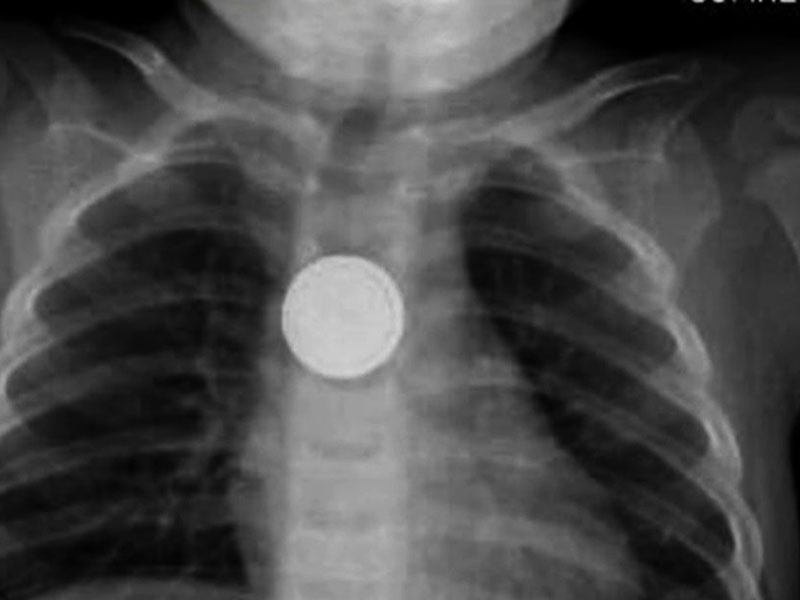

අවුරුද්දක් වයසැති ඇඩෙල් නම් දරුවාගේ අමුතු හැසිරීමකට අනුව ඇයගේ දෙමාපියන් ඇයව එක්ස් රේ පරීක්ෂණයකට ලක්කර තිබුණා.

එහිදී හෙළිව ඇත්තේ බට්න් බැටරියක් ආහාර මාර්ගයේ තැන්පත් වී ඇති අතර ඉන් සිදුවන පිළිස්සුම් සඳහා හදිසි සැත්කම් කිහිපයකට භාජනය කිරීමට සිදුවූ බවයි ඇඩෙල්ගේ දෙමාපියන් පවසා ඇත්තේ.